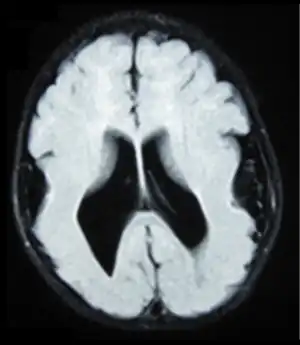

Lissencephaly (/ˌlɪs.ɛnˈsɛf.əl.i/, meaning "smooth brain")[1] is a set of rare brain disorders where the whole or parts of the surface of the brain appear smooth.[2] It is caused by defective neuronal migration during the 12th to 24th weeks of gestation resulting in a lack of development of brain folds (gyri) and grooves (sulci).[3] It is a form of cephalic disorder. Terms such as agyria (no gyri) and pachygyria (broad gyri) are used to describe the appearance of the surface of the brain.

Symptoms of lissencephaly are detected via ultrasound at about twenty-three weeks and require confirmation from a prenatal MRI. It is characterised by absence or reduction of the sulci and gyri of the cerebral surface and a thickened cortex.[5]

There are anatomical symptoms that differ across the two main types of lissencephaly, Classical (Type I) and Cobble Stone (Type 2). In Classical lissencephaly the cortex becomes thickened and can be identified by four layers of the cerebral cortex rather than six.[5]

Cobblestone lissencephaly is named after the pebbled or cobblestone appearance of the cortical surface. This uneven cortical surface is due to incomplete organogenesis which leads to no distinguishable layers in the cerebral cortex. Cobblestone lissencephaly shows a reduction and abnormalities in the grey matter of the cerebral cortex.[5]